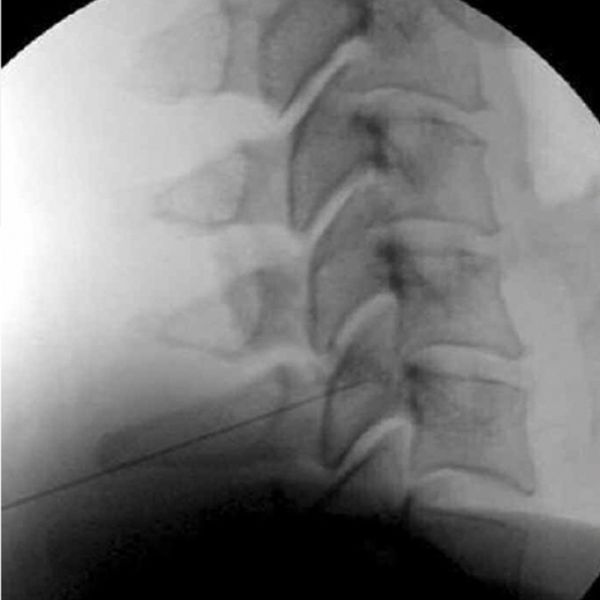

Διαγνωστικός Αποκλεισμός Αποφυσιακών Αρθρώσεων

Η διάγνωση του συνδρόμου των αποφυσιακών αρθρώσεων τίθεται με διαγνωστικό αποκλεισμό των έσω νευρικών κλάδων του οπίσθιου στελέχους του αντίστοιχου νωτιαίου νεύρου, με 0,5 ml τοπικού αναισθητικού. Ο αποκλεισμός εφαρμόζεται υπο ακτινοσκοπική καθοδήγηση.

Κάθε άρθρωση νευρώνεται από δύο τέτοιους κλάδους, έναν από το αμέσως επάνω επίπεδο και έναν από το αμέσως κάτω. Για παράδειγμα για τον αποκλεισμό της Α4-Α5 αποφυσιακής άρθρωσης θα πρέπει να αποκλειστούν οι έσω κλάδοι των Α4 καιΑ5 οπίσθιων νευρικών στελεχών των αντίστοιχων νωτιαίων νεύρων.